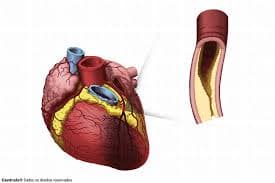

Antes de mais nada, a Cardiologia clínica concentra o cuidado médico contínuo do coração, com foco em prevenção, diagnóstico preciso e acompanhamento individualizado.Além disso, a especialidade […]

Antes de mais nada, a Cardiologia reúne práticas essenciais para prevenção, diagnóstico e acompanhamento das doenças do coração.Além disso, a especialidade orienta decisões clínicas baseadas em […]

Antes de mais nada, o Tratamento para Doença Arterial Coronária reduz riscos cardíacos ao controlar placas nas artérias e melhorar a circulação do sangue no coração.Além […]

Antes de mais nada, Infarto do Miocárdio ocorre quando o fluxo de sangue para o coração diminui ou bloqueia totalmente, causando lesão no músculo cardíaco.Além disso, […]

Antes de mais nada, Doença Arterial Coronária representa uma das principais causas de infarto e morte cardiovascular no Brasil, exigindo diagnóstico rápido e acompanhamento especializado.Além disso, […]